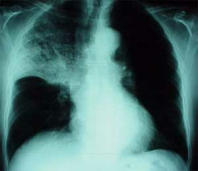

El

grupo sanguíneo A tiene una sobreproducción de

mucílago lo que es siempre un grande riesgo

para infecciónes, hasta la pulmonía.

El grupo sanguíneo A tiene un problema crónico de mucílago y así el grupo A está siempre propenso a infecciones: Sinusitis, bronquitis y pulmonía etc.

Ejemplo: Radiografía con una pulmonía al lóbulo de pulmón superior con sombra en el centro  de la región derecha del pulmón.